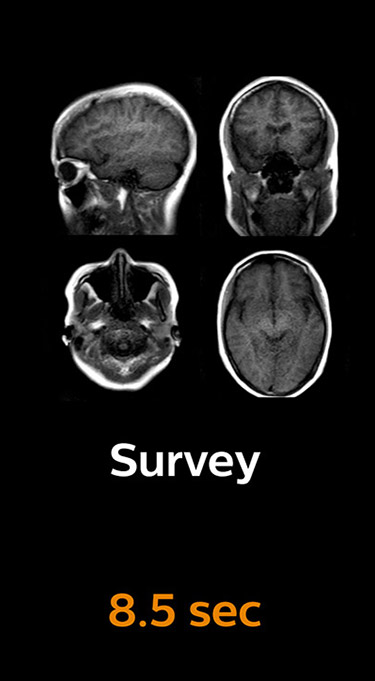

Scanning time reduction in brain MRI with Compressed SENSE

With Compressed SENSE, the scan time for the routine brain examination at KNC was reduced from 15:48 to 10:19 minutes, which corresponds to 35% reduction.

Ingenia 3.0T CX

Scan time 15:48 min.

Brain with Compressed SENSE

Scan time 10:19 min.